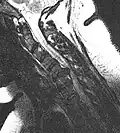

L'imagerie par résonance magnétique peut montrer la hernie, le canal vertébral, les nerfs, les tissus environnants. Les tissus mous sont les mieux analysés par cet examen qui est le plus performant pour le diagnostic de hernie discale. Les images pondérées en T2 montrent clairement la hernie.

IRM lombaire sagittale montrant une hernie discale de niveau L4-L5.

IRM lombaire sagittale montrant une hernie discale de niveau L4-L5.- IRM lombaire sagittale montrant des protrusions discales.